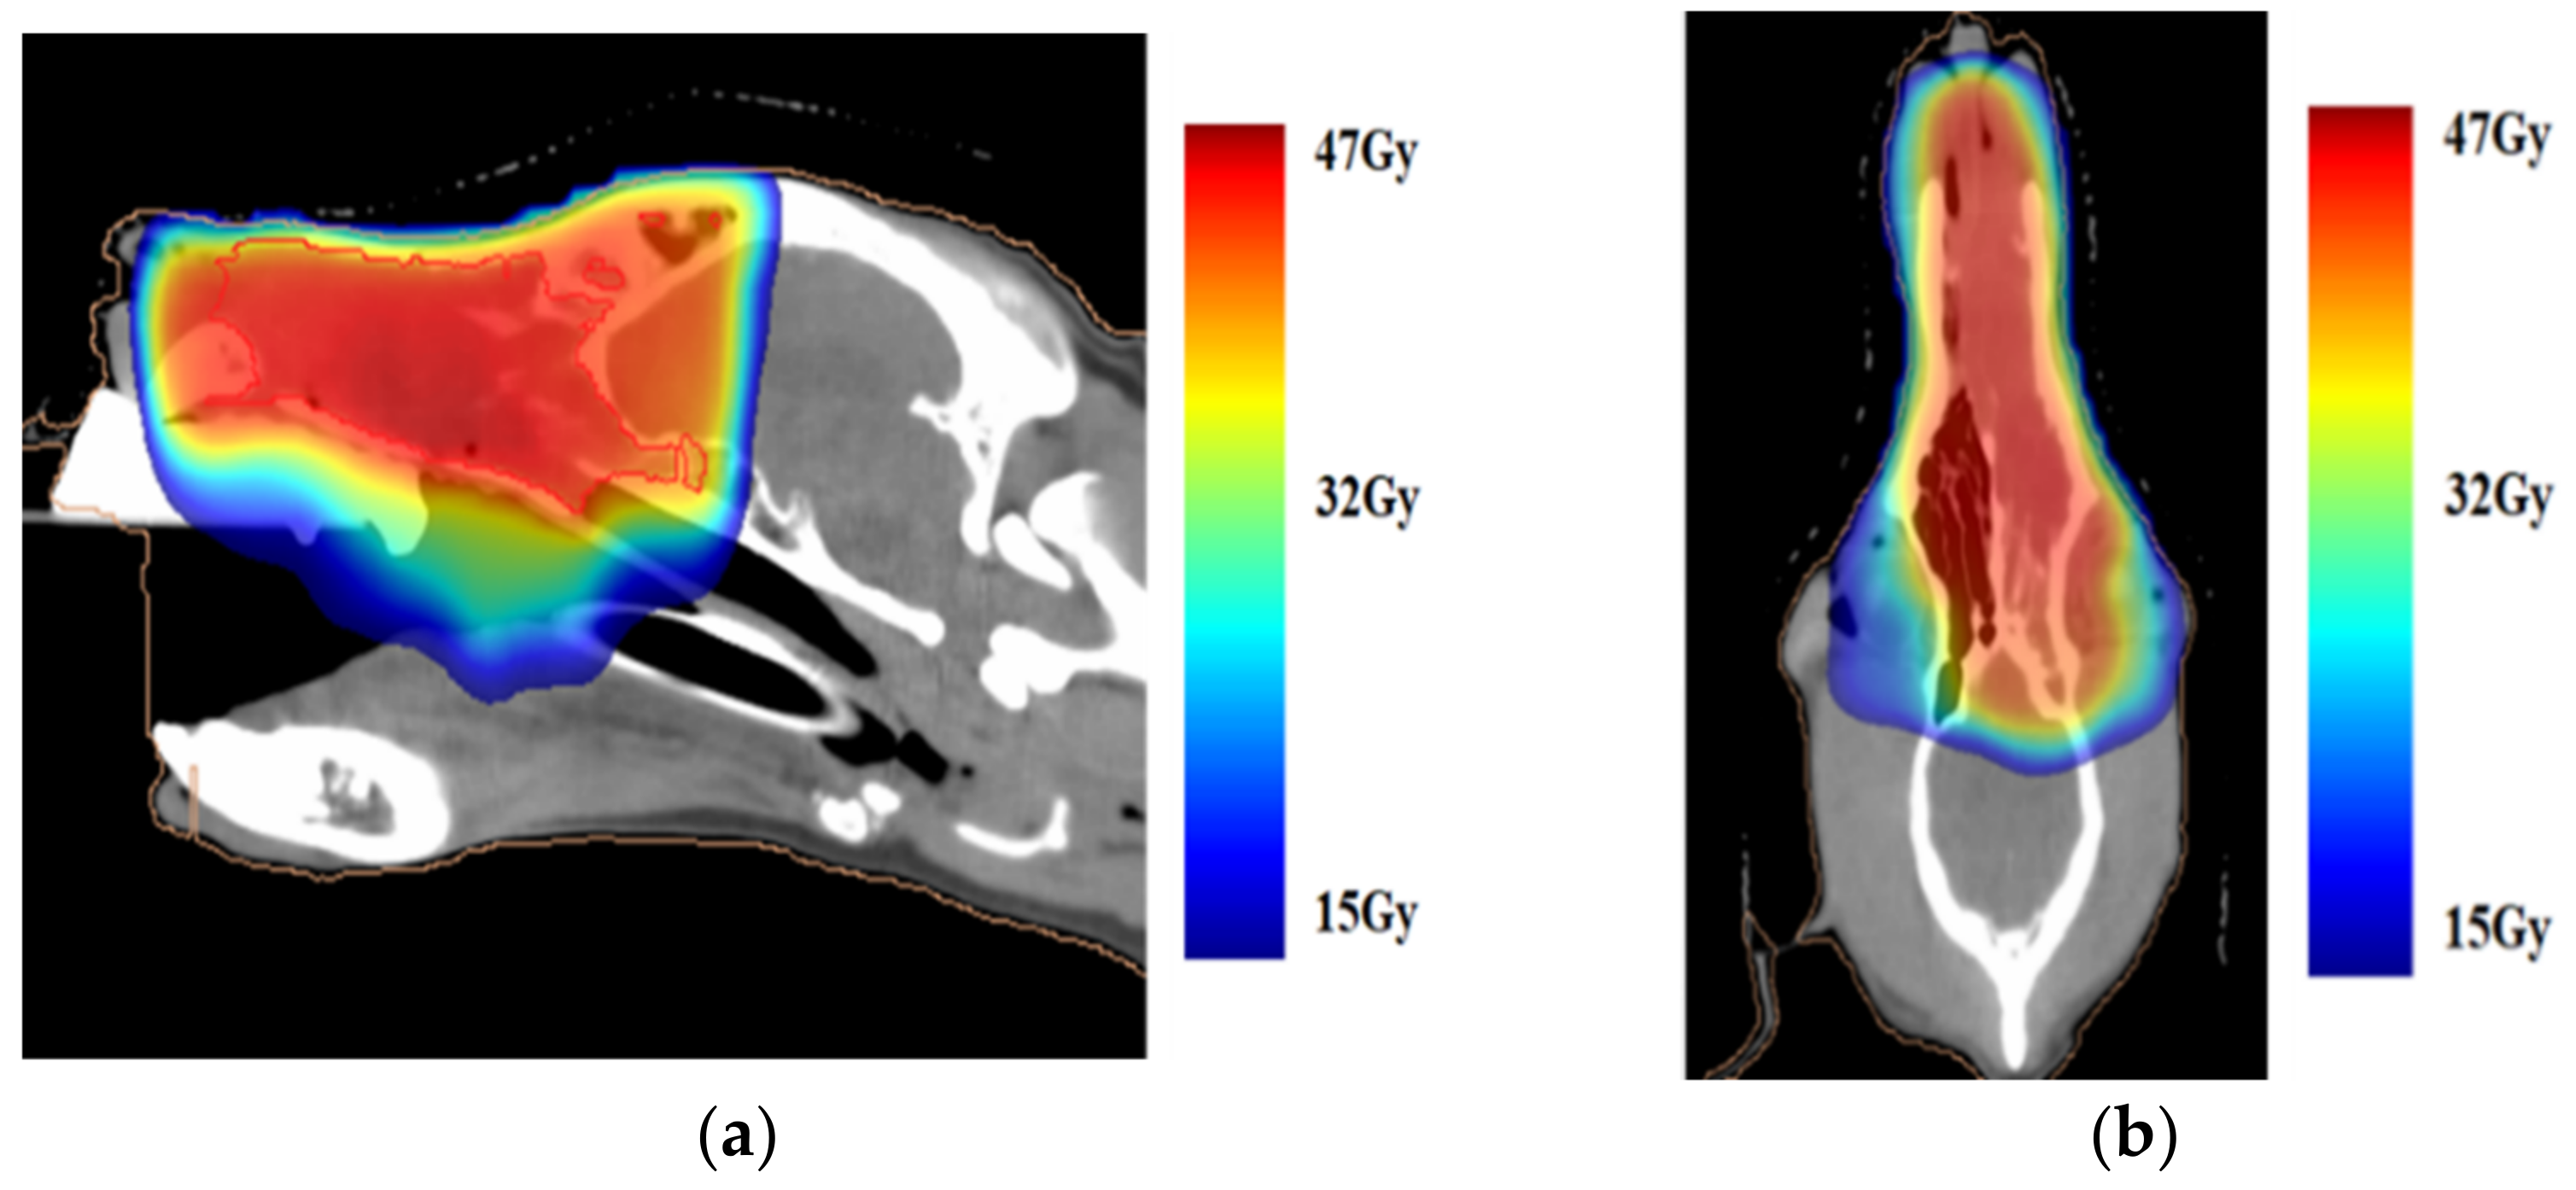

2.1. Case Presentation